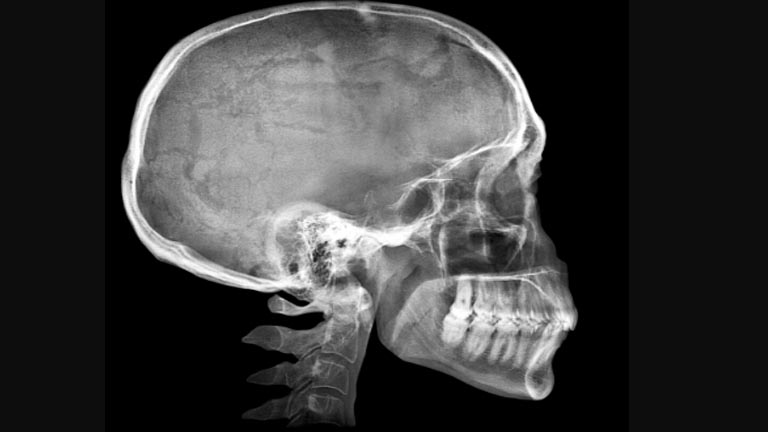

La craniectomia decompressiva è un intervento chirurgico che prevede l’asportazione di parte della calotta cranica con successiva apertura delle meningi cerebrali.

Questo intervento viene preso in considerazione, come ultimo step, quando una patologia cerebrale determina un aumento notevole della pressione all’interno della teca cranica che non controllabile con la terapia medica e che mette a repentaglio la vita del paziente. Asportando l’osso si ottiene l’apertura di un contenitore chiuso e inestensibile che è il cranio e la successiva riduzione della pressione intracranica.

Un ultimo aspetto come evoluzione tecnica è la possibilità, ormai consolidata da anni, di ricostruire, in pazienti selezionati, la calotta cranica asportata, creando in laboratorio protesi craniche su misura di vari materiali che vengono impiantati con un secondo intervento chirurgico che viene chiamato cranioplastica.